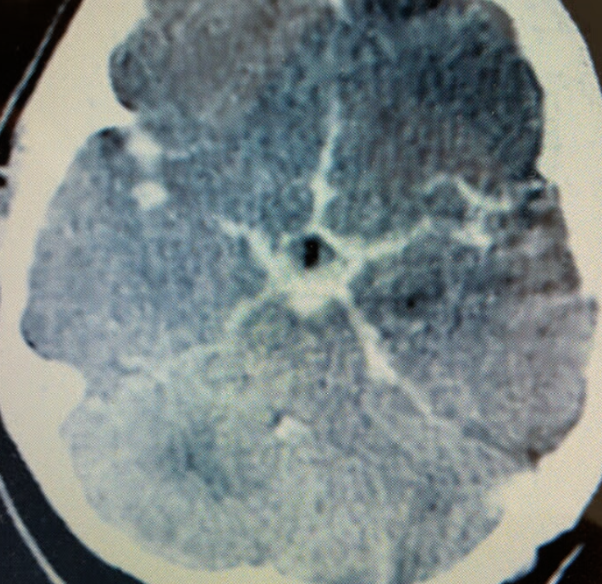

Case 12

A 54-year-old woman presented with a sudden onset thunderclap headache and neck pain for 2 days.

What is the abnormality in the image shown?

a. Blood mixed with CSF filling the subarachnoid space -

What is the likely diagnosis?

a. Subarachnoid hemorrhage -

b. Hyper dinse lesion -

a. Meningitis